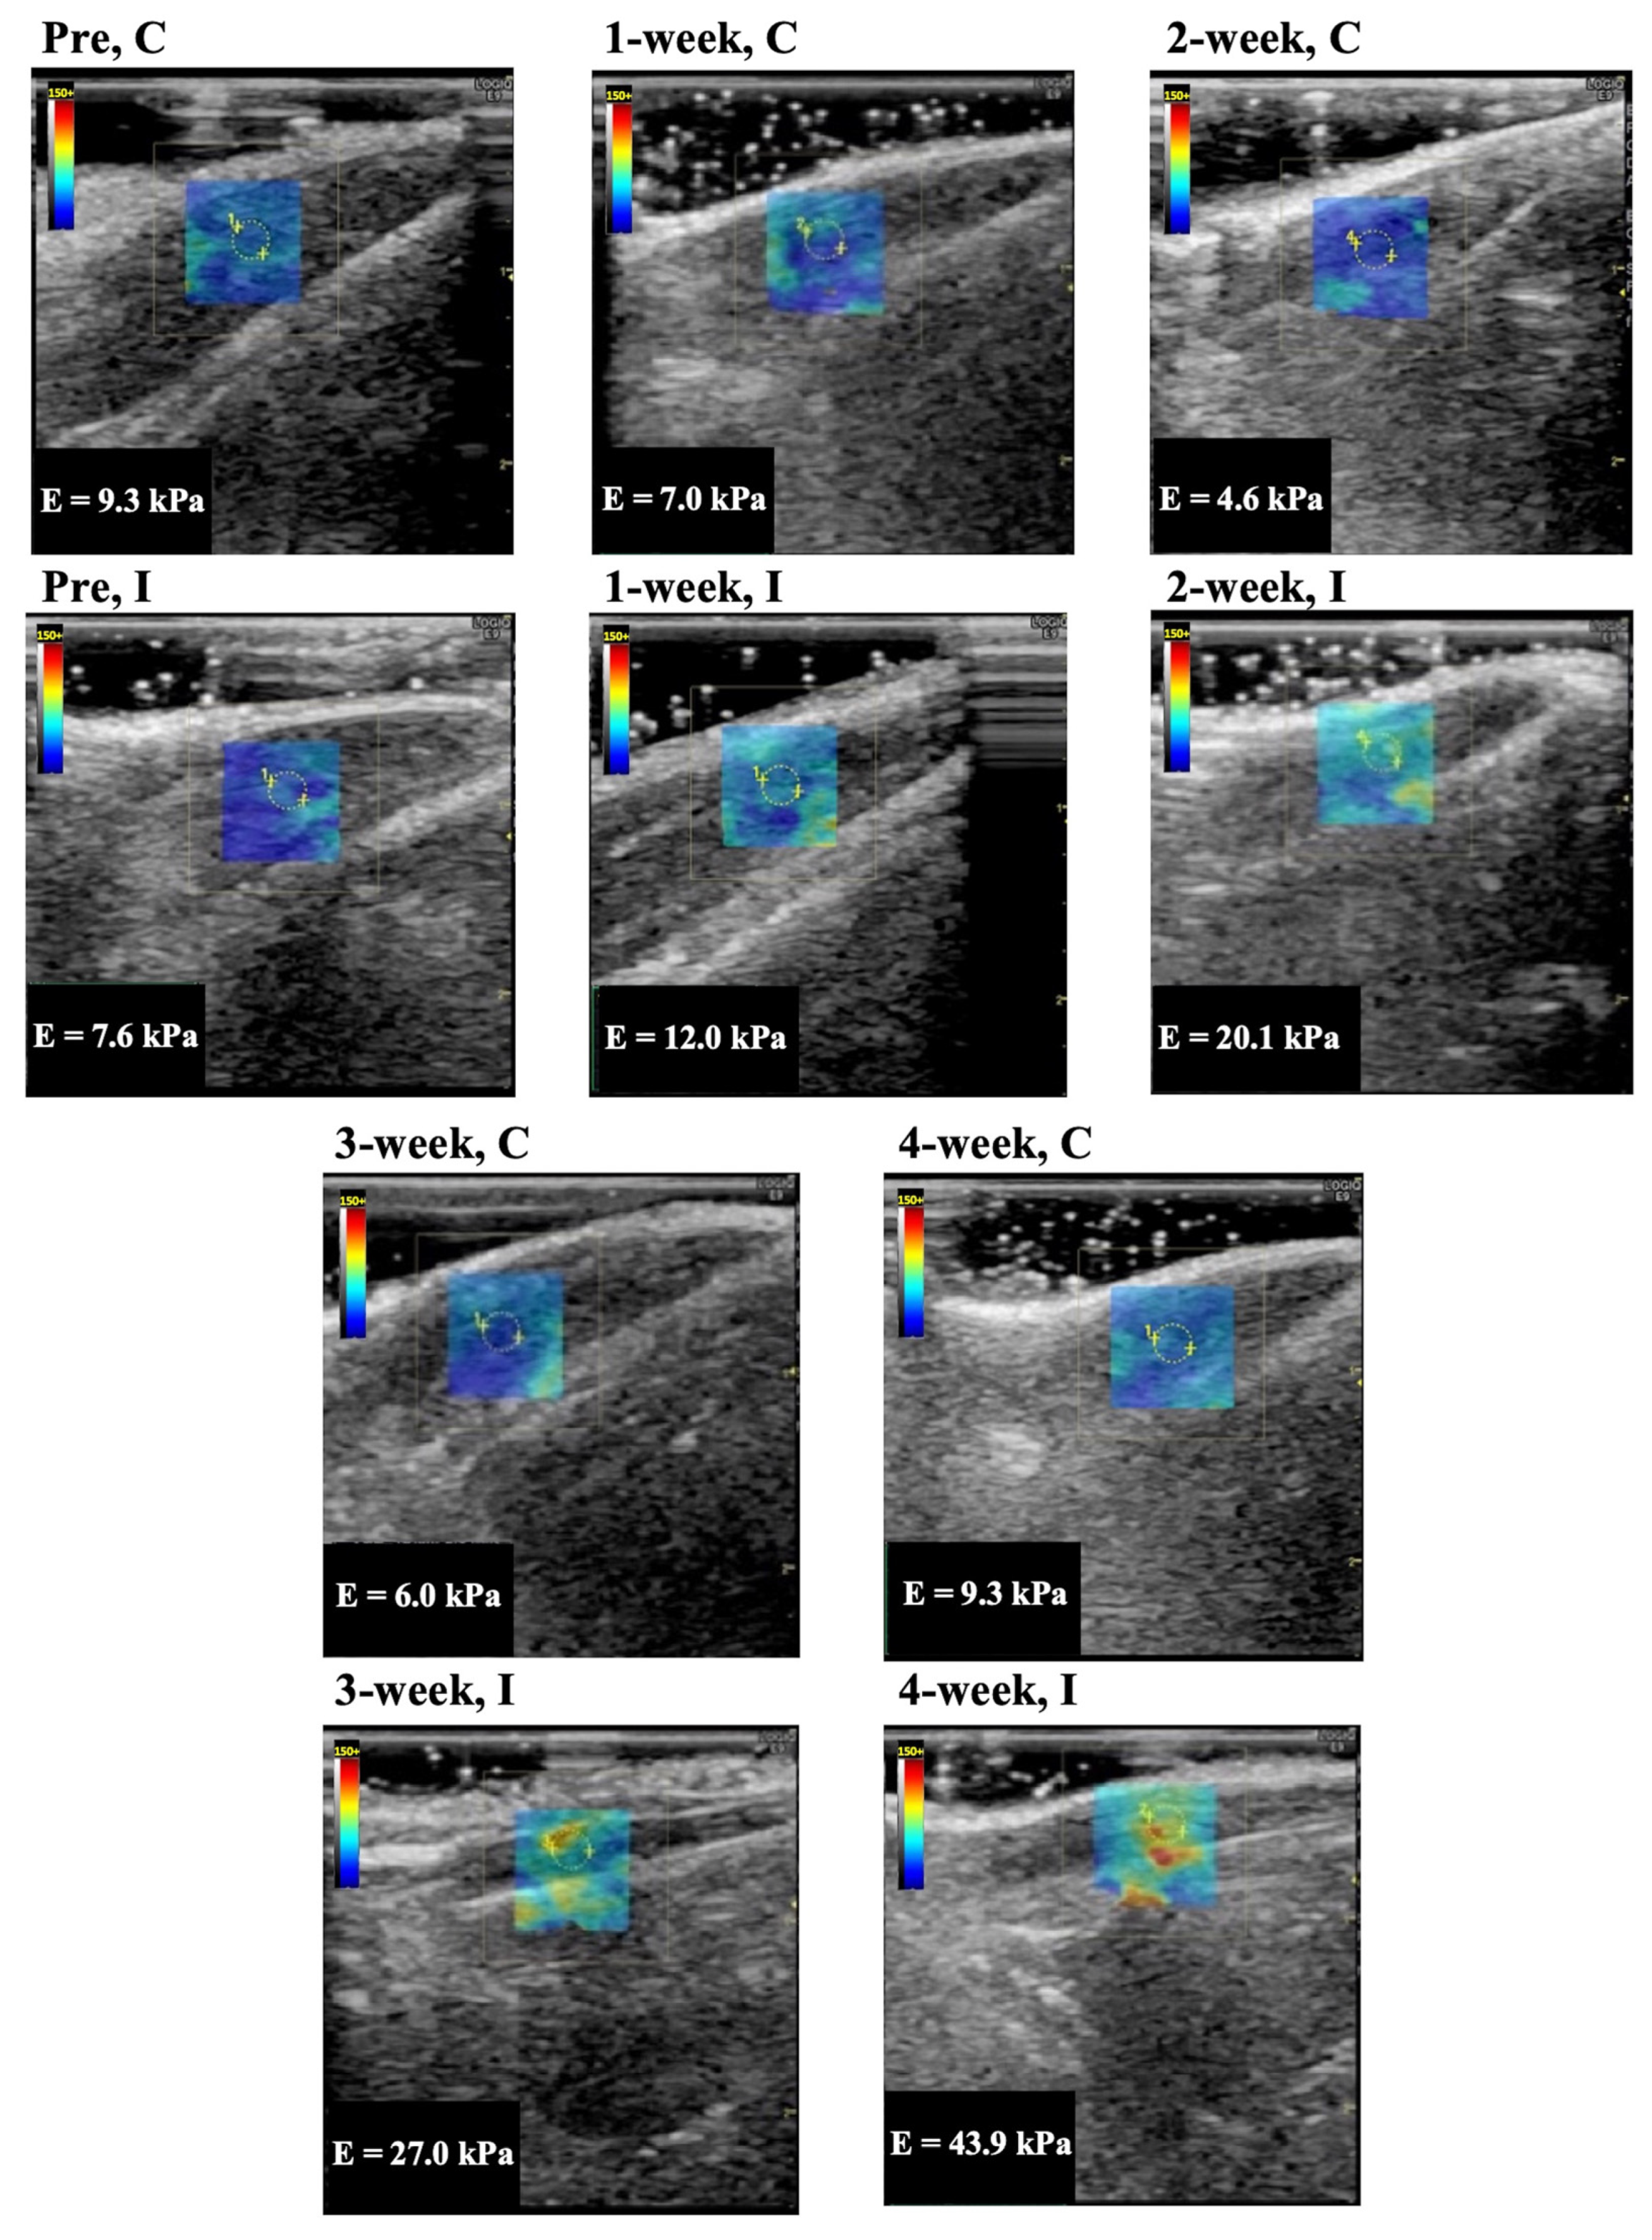

Representative longitudinal ultrasound shear wave elastography images of the rectus femoris, vastus lateralis, and vastus medialis muscle are shown in Figure 2, Figure 3, and Figure 4, respectively. In Group I, cyan, orange, and red colors increased during the immobilization period, suggesting an increased elastic modulus.

The elastic modulus of the rectus femoris, vastus lateralis, and vastus medialis muscle as determined by ultrasound shear wave elastography are shown in Figure 5A–C. The elastic modulus of the rectus femoris, vastus lateralis, and vastus medialis muscles in Group C were 8.6 ± 1.0, 7.4 ± 1.3, 7.6 ± 1.1 kPa (mean and standard deviation) in before experiment, 7.5 ± 1.4, 7.8 ± 0.8, 8.7 ± 0.5 kPa in 1 week, 7.4 ± 1.2, 7.1 ± 1.6, 8.0 ± 1.5 kPa in 2 weeks, 8.6 ± 1.2, 7.5 ± 0.9, 8.4 ± 0.7 kPa in 3 weeks, and 8.0 ± 1.0, 7.4 ± 1.0, 8.5 ± 0.7 kPa in 4 weeks, respectively. The elastic modulus of those muscles in Group I was 8.3 ± 1.2, 7.4 ± 1.1, 7.7 ± 1.1 kPa in the before experiment, 15.0 ± 1.4, 15.2 ± 2.2, 14.5 ± 1.5 kPa in 1 week, 20.1 ± 1.7, 19.6 ± 2.2, 18.9 ± 2.5 kPa in 2 weeks, 29.0 ± 2.1, 28.8 ± 1.7, 29.2 ± 2.4 kPa in 3 weeks, and 30.6 ± 2.7, 32.9 ± 4.0, 33.1 ± 3.4 kPa in 4 weeks, respectively. The elastic modulus for all periods in Group I was significantly higher (p = 0.0001 in all muscles) compared with the same periods in Group C. In Group I, the elastic modulus increased after more than 3 weeks of immobilization compared to the 1 and 2 week immobilizations.

Figure 3. Representative shear wave elastography of the vastus lateralis muscle. C, control group; I, immobilization group; Pre, before the experiment; E, elastic modulus. The rectangle indicates the region of interest. The measurement circle was 2 mm in diameter.